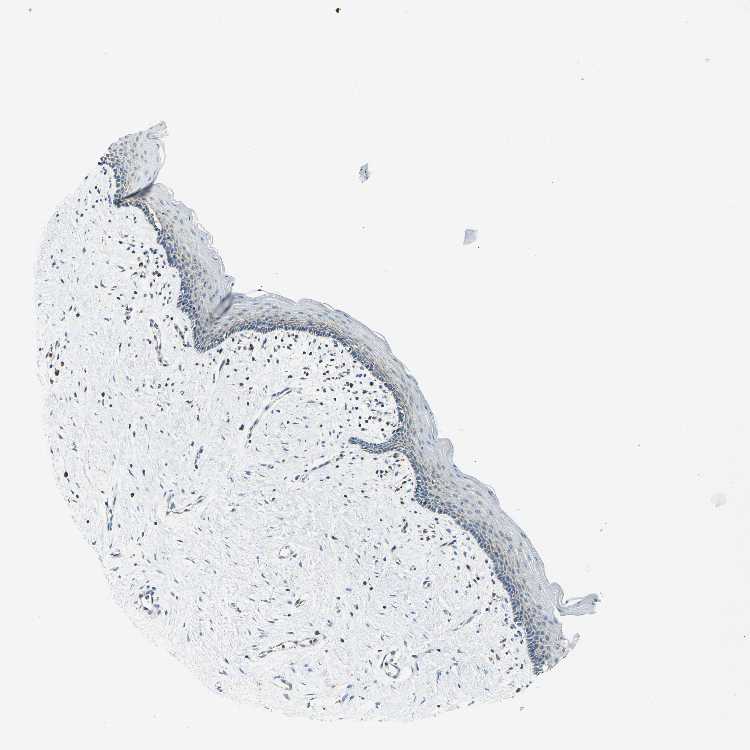

VAGINA - Antibody stainingi

Antibody staining in the annotated cell types in the current human tissue is reported as not detected, low, medium, or high, based on conventional immunohistochemistry profiling in selected tissues. This score is based on the combination of the staining intensity and fraction of stained cells.

Each image is clickable and will lead to virtual microscopy that enables deeper exploration of all samples and also displays staining intensity scores, fraction scores and subcellular localization as well as patient and tissue information for each sample.

Antibody HPA004895Antibody CAB013018

Squamous epithelial cells LowLow